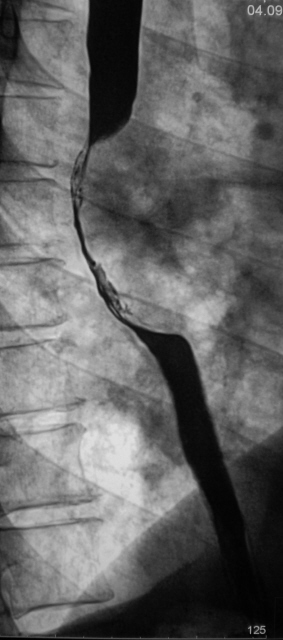

Линейные томограммы в боковой проекции

По представленным снимкам, у меня сложилось впечатление что пищевод как бы сдавлен извне (овал), возможно образованием в заднем средостении; при этом на довольно продолжительном участке есть нарушение архитектоники складок слизистой с множественными участками barium depletion (стрелки), свидетельствующими в пользу изъязвления.

Выводы: изначально хотелось бы узнать анамнез и жалобы; но так как их не представлены, буду рассуждать опираясь только на семиотику. У меня 2 варианта: опухоль пищевода с преимущественно интра-муральным ростом или образование средостения с прямой инвазией пищевода вплоть до слизистой оболочки, в данном случае может быть много вариантов. Моя рекомендация-конечно КТ, посмотреть стенки пищевода и окружающие структуры.

Исходя из вышесказанного, по данному случаю: сдавление просвета и смещение пищевода мягкотканным образованием, выходяшим за пределы стенки, изъязвление передней стенки пищевода. Заключение: подслизистая опухоль пищевода с изъязвлением, вероятнее всего лейомиома. Рекомендации: эндоУЗИ с биопсией, КТ.

После проведенного рентгенологического исследования органов грудной полости - рентгенографии и томографии, при которой были выявлены увеличенные лимфатические узлы в корнях лёгких и средостении, было проведено рентгенотелевидение пищевода с прицельной рентгенографией и исследованием пищевода на трохоскопе, с контрастированием пищевода водной взвесью сернокислого бария "различной консистенции" - от сверхжидкого - до пастообразного, для "выяснения состояния" заднего средостения. Была зарегистрирована и документирована "локальная деформация пищевода" на протяжении 9,5 см. с перестройкой структуры "рельфа слизистой оболочки".